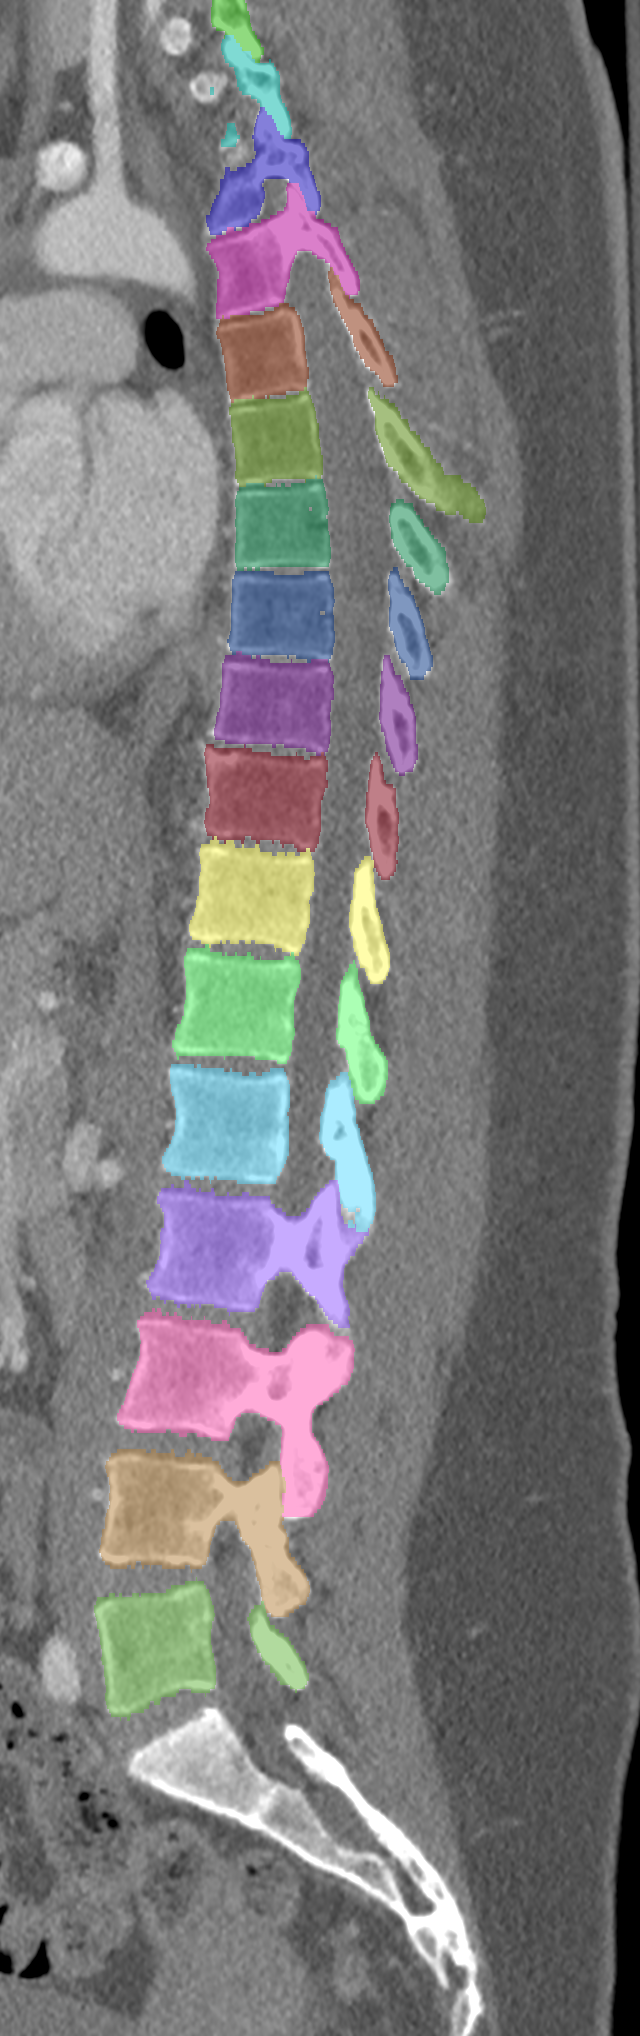

Normalized CT images and reference segmentations of thoracic and lumbar vertebrae from the CSI 2014 workshop

This is the dataset of the vertebra segmentation challenge of the CSI 2014 workshop that was held in conjunction with MICCAI 2014.

- Vertebrae have been anatomically labeled (8 = T1, 9 = T2, ..., 24 = L5)

- Because not always all visible vertebrae were segmented in the original data, only segmentations of the thoracic and lumbar vertebrae have been retained